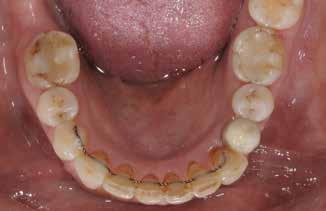

Vi viser her to ortodontiske behandlinger af patienter med velbehandlet stadie 3- og 4-parodontitis, som begge har tandtab og reduceret, men sundt parodontium, dog med begrundet undtagelse af en enkelt tand, som vi kommer tilbage til. Behandlingerne følger følgende princip:

PATIENTTILFÆLDE 1

Patienttilfælde 1 (Fig. 1) er en 37-årig kvinde, henvist efter succesfuld behandling af stadie 3-parodontitis. Der er nu sundt

Før behandling

parodontium, ingen pocher over 4 mm, og både blødnings- og plakindeks er under 10 %. Patienten er motiveret for ortodontisk behandling, da hendes tænder er vandret over tid, delvist som følge af reduceret parodontium.

Der ses anterior trangstilling i begge kæber og overerupterede 1+1 og 2,1-1,2, hvilket resulterer i dybt bid med 2- tæt på ganepåbidning. Der er normale sidetandsrelationer, men der ses 5 mm horisontalt overbid (HOB) og 7 mm vertikalt

overbid (VOB). Papillen mellem 1+1 er betydeligt reduceret pga. fæstetab, og de mesialt kippede 1+1 har resulteret i en ”dark triangle”. Den facioorale funktion er for nuværende i.a. Panoramarøntgen (Fig. 1, I) viser marginalt knogletab i begge kæber og fravær af 8,7+7,8 og 8,7-8.

Der planlægges alignerbehandling af begge kæber med intrusion af 1+1 og 2,1-1,2, nivellering af trangstilling UK med interproksimal reduktion (IPR) (Fig. 2 A, B) og senere IPR OK for reduktion af dark triangles mellem incisiverne efter nivellering. Patienten instrueres i at benytte alignere 20-22 timer/ dag med alignerskift hver 7. dag, og patienten ses hver 3.-8. uge under forløbet. Den første alignerserie består af 16 alignere for nivellering OK/UK og IPR i UK (Fig. 2). Efter denne serie planlægges IPR mellem incisiverne i OK for reduktion af dark triangles (Fig. 3) samt yderligere intrusion af OK og UK-fronten i 12 refinement-alignere. Patienten udviser god kooperation og er meget tilfreds med alignerapparaturet, som er mindre synligt end det faste apparatur (Fig. 4).

Behandlingen afsluttes med yderligere refinement-alignere for finindstilling af okklusionen, og efter 11 måneders ortodontisk behandling er der opnået normale relationer i alle tre